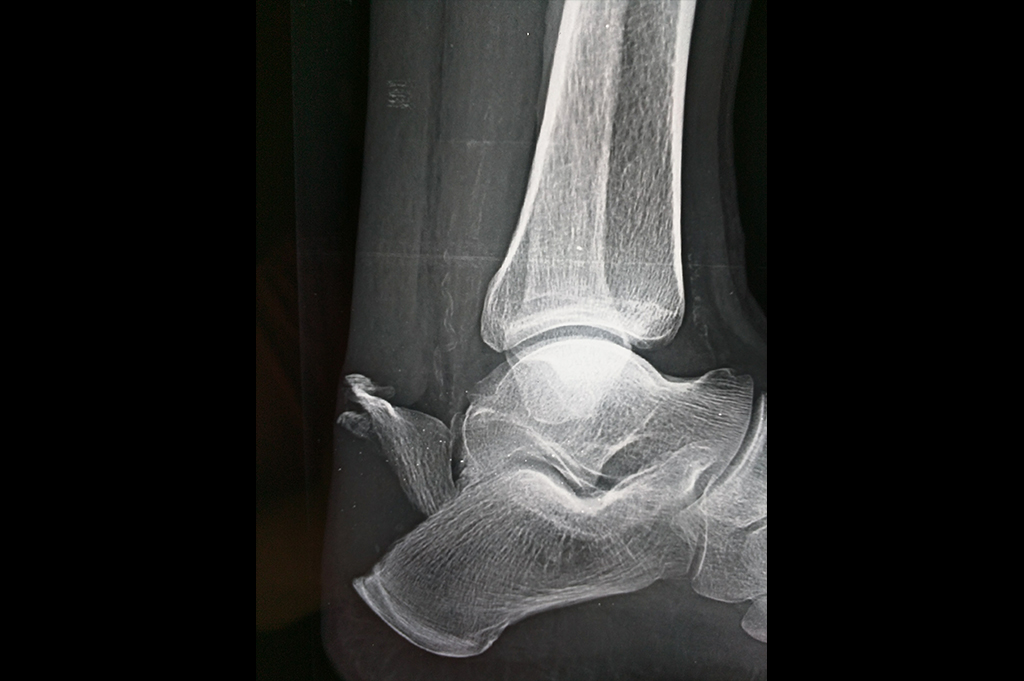

Ankle